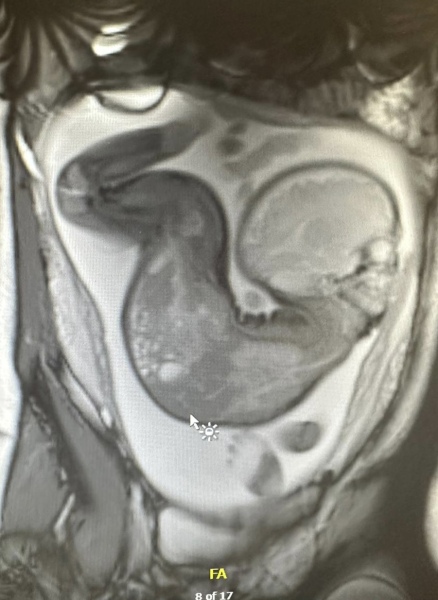

Hyperextension of fetal neck and spine

We were referred to fetal medicine unit in Leeds last year due to our baby’s unusual position at 32 weeks. He was found during a routine scan to be in a star gazing position which is essentially hyperextension of the neck and spine. After various tests and scans including an MRI, we were unable to determine if the baby would encounter any challenges when born. The baby didn’t change positions and was delivered by planned c-section at 38 weeks, 24/04/2023.

What a fantastic story, thank you for sharing and I'm so pleased that your son is happy and thriving. I have never come across anything like this, those images are extreme!!!